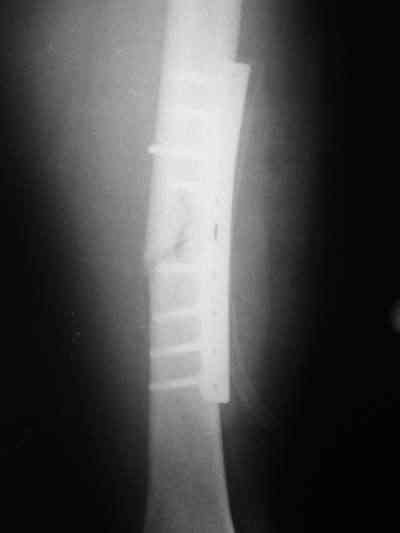

Около 10 дней назад выполнил остеосинтез бедренной кости LC-DCP и DHS по поводу фрагментарного оскольчатого перелома в средней трети и чрезвертельного перелома.

Снимки в приложении.

В приложении и имеющийся в наличии брейс. Приношу извинения за низкое качество снимков.

Качество снимков приемлемое. С нагрузкой категорически не надо спешить - только при уверенных рентгенологических признаках сращения на обоих уровнях в данном случае. Т.е. не только на диафизе, но и в вертельной области. При безупречном синтезе DHS ранняя нагрузка в этой зоне была бы безопасна, все определялось бы сращением диафиза. А поскольку винт в DHS сделали ну о-очень короткий, то ойкнуть не успеете, как

проксимальный отдел бедра в варус кувыркнется.

Глубокоуважаемый Никита!На бедре стоило бы обязательно провести межфрагментарный стягивающий винт и предварительно надо бы слегка изогнуть пластину,ну и может быть трансплантат по внутренней поверхности.А параллельно большому винту DHS провести спонгиозный винт для ротационной стабильности.Так,что с нагрузкой не нада тараписся!

Алексей Семенистый 28 Июль 2006, 20:08

Уважаемый Никита, очень меня расстроило не качество снимков, а сам остеосинтез. Вертельный перелом, пожалуй, еще срастется. А диафиз может преподнести ожидаемое, предуготованное осложнение: несращение и перелом импланта, даже если это суперфмрменная пластина.:(